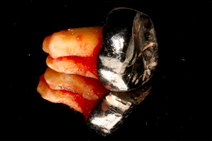

- Surgical removal of excessive gum tissues and extraction of multiple poor prognosis teeth were carried out as well